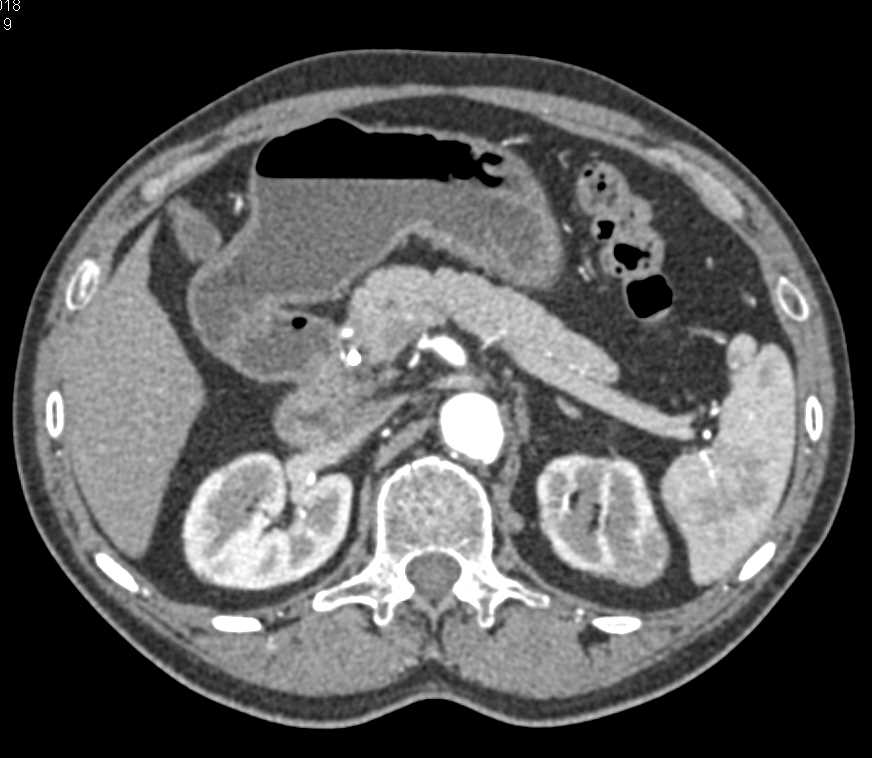

Subtle Lymphoma Left Kidney